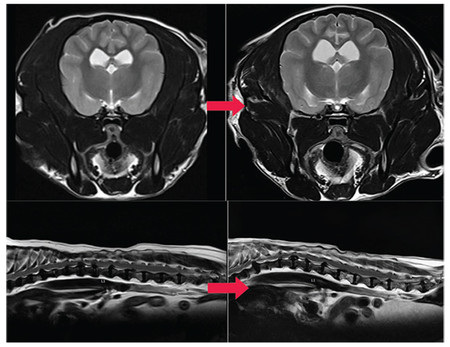

이안동물의학센터 측은 “AI 소프트웨어는 자가공명영상의 물리 법칙과 인공지능의 딥러닝 기술을 결합해 촬영된 이미지를 재구성함으로써 촬영시간 단축과 함께 노이즈를 개선하고 선명도를 향상시켰다”고 밝혔다.

AI 도입 후 이안은 한 시퀀스당 소요되는 촬영 시간을 최대 절반으로 단축해 이전보다 더 신속하게 촬영하고 있다.

또한 획기적인 딥러닝 AI 기술을 통해 이미지를 재구성하여 노이즈를 개선하고 선예도를 향상시켰다고 전했다.